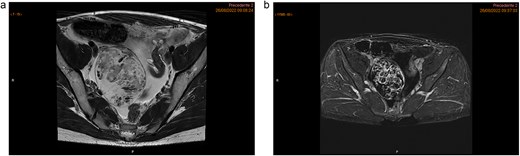

The MRI showed a heterogeneous right adnexal mass with mixed solid and cystic components. Moderate ascites was present in the subphrenic and paracolic gutters as well as the pelvic recesses. No suspicious lymphadenopathy or peritoneal thickening was observed on MRI (Fig. 1a and b). The subsequent CT scan confirmed a complex right ovarian lesion measuring approximately 80 × 67 × 57 mm, with solid contrast-enhancing components, highly suspicious for malignancy. Ascites and an indeterminate omental nodule were also noted. Additionally, subtle fat stranding in the omentum (in the lower portion of the greater omentum adjacent to the bladder), along with the moderate ascites, suggested early peritoneal carcinomatosis (Fig. 2).

Pelvic MRI highlighting a heterogeneous right ovarian lesion with high signal on axial T2 WI (a), and irregular enhanced septum on DCE T1 WI (arrow). Ascites and a pelvic nodule with fat and contrast enhancement (arrow head) (b).